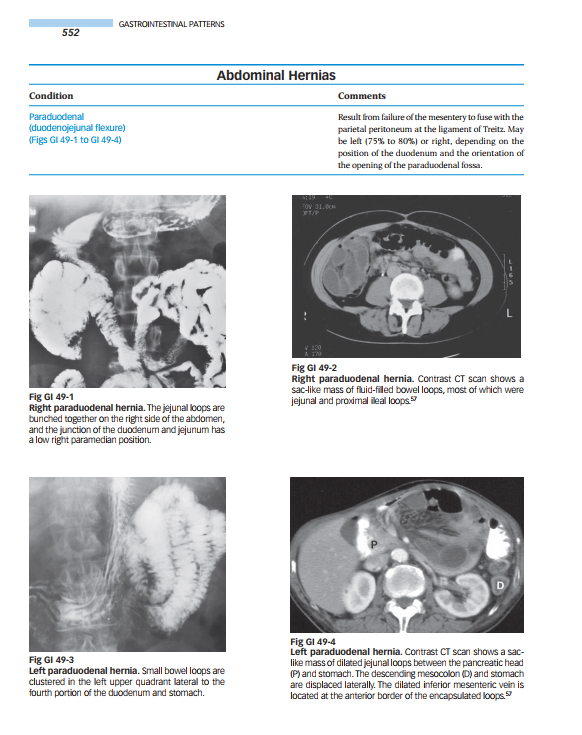

Organized by anatomic area, the book outlines and illustrates typical radiologic findings for every disease in every organ system. Tables on the left-hand pages outline conditions and characteristic imaging findings…and offer comments to guide diagnosis. Images on the right-hand pages illustrate the major findings noted in the tables.